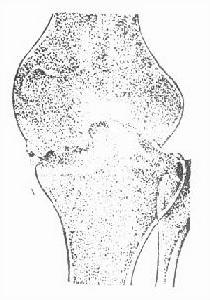

骨結核多發生在股骨下端骨骺或乾骺部及脛骨上端的內外兩髁,分為中心型和邊緣型兩種。中心型病變常易產生死骨,死骨吸收後形成空洞,邊緣型病變好發於乾骺部,死骨較少見。單純骨結核穿破軟骨進入關節累及滑膜,則變為全關節結核。位於關節附近的邊緣型病變更易侵入關節內,造成全關節結核。腓骨頭結核及脛骨結節結核均較少見。髕骨結核也少見,也分中心型和邊緣型兩種,一般髕骨結核容易穿破關節面,造成全關節結核。

(1)單純滑膜結核:X線片可表現為髕上囊擴大或髕上髕下和膝後滑膜囊的增生肥厚,病程較長的有時可見因脂肪墊水腫及炎性細胞的浸潤而使髕下脂肪墊透明陰影消失。另外,股骨下端及脛骨上端可出現普遍的骨質疏鬆。關節間隙可因較多的關節積液或滑膜增生肥厚而擴大或狹窄。在膕後三角組織脂肪內的淋巴腫大在X線片上看到有結節狀密度增高影(2)單純骨結核:早期膝關節周圍軟組織層次不清,晚期則主要表現為腫脹。骨骼改變為中心型和邊緣型結核兩種,常見於股骨下端和脛骨上端,髕骨結核少見。中心型病變多見於股骨和脛骨的乾骺端或骨骺,早期顯示骨稀疏模糊,後期則因病灶滲出骨壞死及乾酪病灶中的鈣沉積,X線片可呈磨砂玻璃樣改變。以後死骨游離,死骨吸收後形成骨空洞。如有乾酪樣物栓塞動脈時,可出現大塊緻密的死骨。中心型結核的特點是不受骺板限制,病灶可跨越骨骺及乾骺端的偏心型破壞。邊緣型主要表現在骨質邊緣區的蟲蛀樣溶骨破壞,一般無死骨,髕骨的中心型結核的松質骨可大部分破壞,僅留骨外殼,有的還稍有膨脹,很似骨巨細胞瘤。

(3)全關節結核:早期來自滑膜結核的全關節結核除了有滑膜結核的X線特點外,還可在骨質邊緣見到小而局限的溶骨破壞,來自單純骨結核者,則可見到滑膜腫脹及附近骨質的接觸性破壞。早期的全關節結核軟骨下骨板大部分保持完整,關節間隙正常或稍窄。

晚期全關節結核除上述早期改變外,可見骨破壞明顯增加,軟骨下骨破壞消失,關節間隙狹窄或消失,嚴重者可有骨性強直。畸形還可見病理性脫位,膝關節屈曲及內外翻,兒童患者可見股骨和脛骨的發育障礙,長期的混合感染可見到骨質增生硬化性改變,存在時間較長的冷膿腫可發生鈣化。